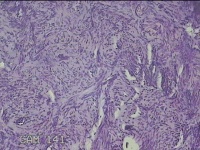

宫腔内容物

性别

女

年龄

45岁

临床诊断

子宫内膜息肉

一般病史

月经量增多10年,B超检查发现宫腔异常回声半月余。

标本名称

大体所见

灰白暗红色不规则碎组织1.5x1.3x0.7cm一堆。